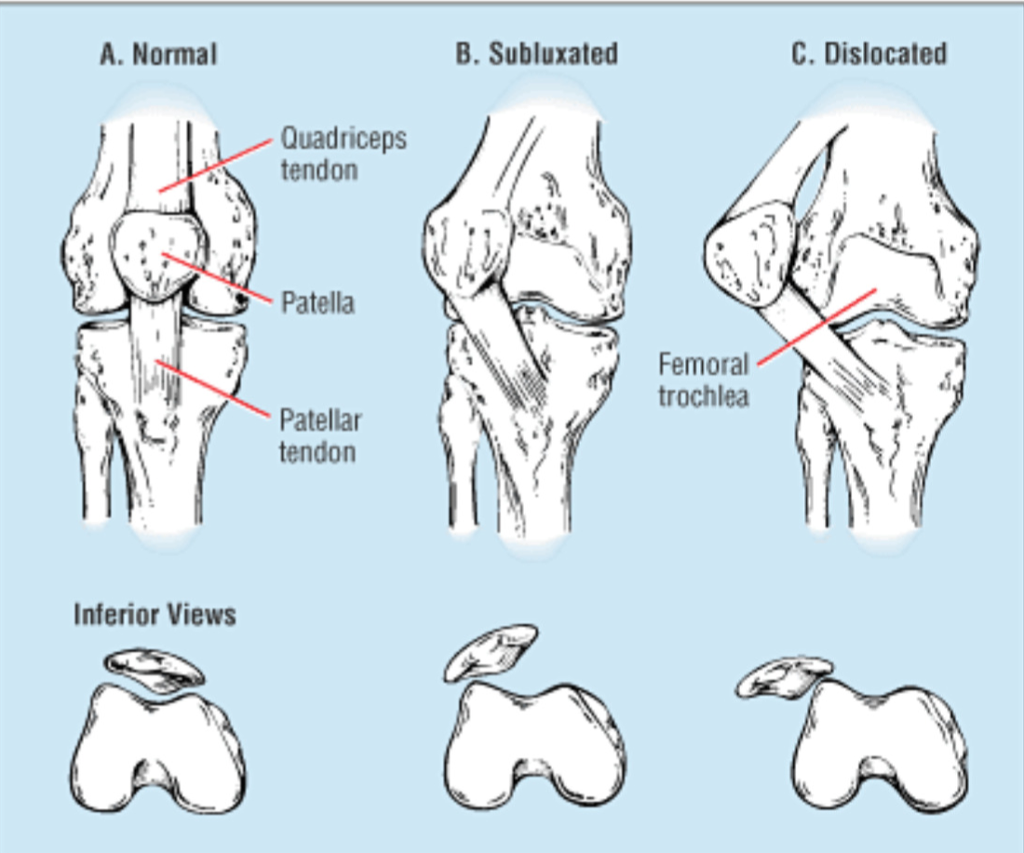

22. 외측 슬개골 탈구의 징후에 대해 열거하라.

• 외측 대퇴과의 후외측 방면과 내측 슬개골 후관절의 내측 방면에서의 상호간 골 타박상

• 슬개대퇴 연골 손상

• 내측 슬개지대 또는 내측 슬개대퇴인대 또는 양쪽 모두의 손상

• 관절 삼출액

얕은 슬개골 절흔의 존재는 이러한 손상이 초래되는 경향이 있을 수 있다. (그림 46-10)

△ 슬개골 불안정성 (Patella Instability)

(이미지 출처 : http://kneeandshoulderclinic.com.au/knees/surgical-conditions/patella-instability/)